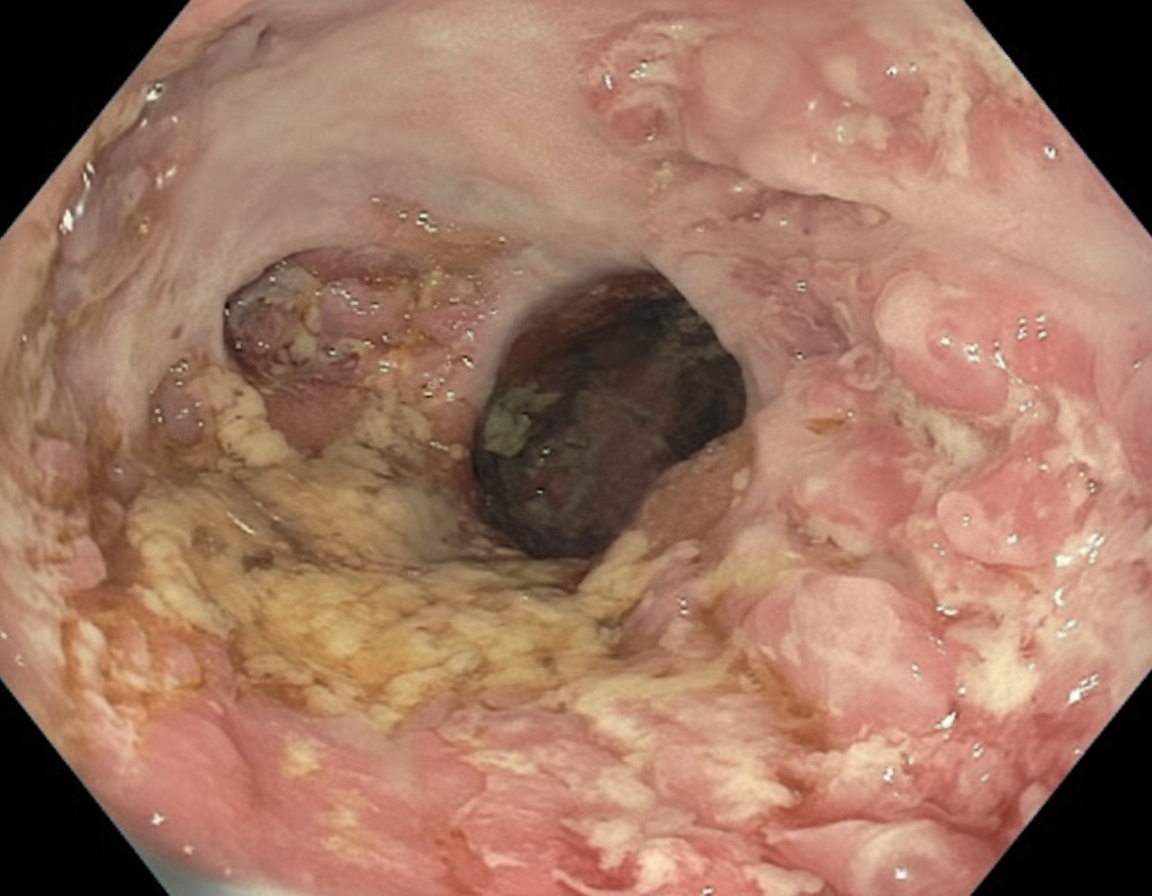

A 28-year-old man comes to the physician because of a 6-month history of progressive fatigue and intermittent diarrhea. During this time, he has had a 6-kg (13-lb) weight loss. Physical examination shows pale conjunctivae. Abdominal examination shows tenderness to palpation in the lower quadrants. An image from a colonoscopy of the descending colon is shown. Further evaluation is most likely to show which of the following findings?